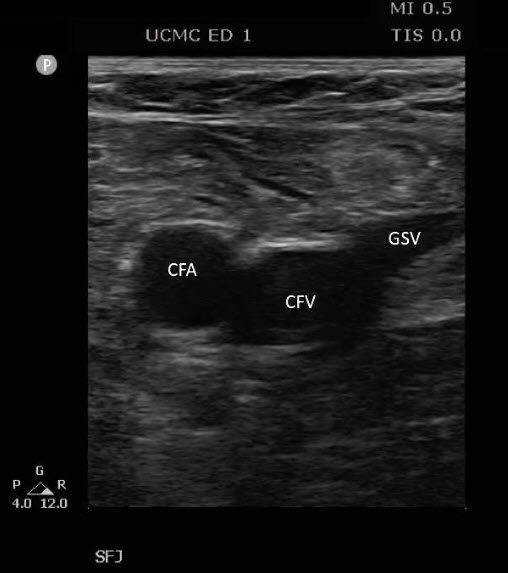

Describe the anatomical placement of the GSV, CFA, CFV